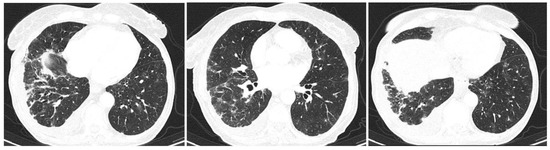

2. Clinical Experience—Case Report